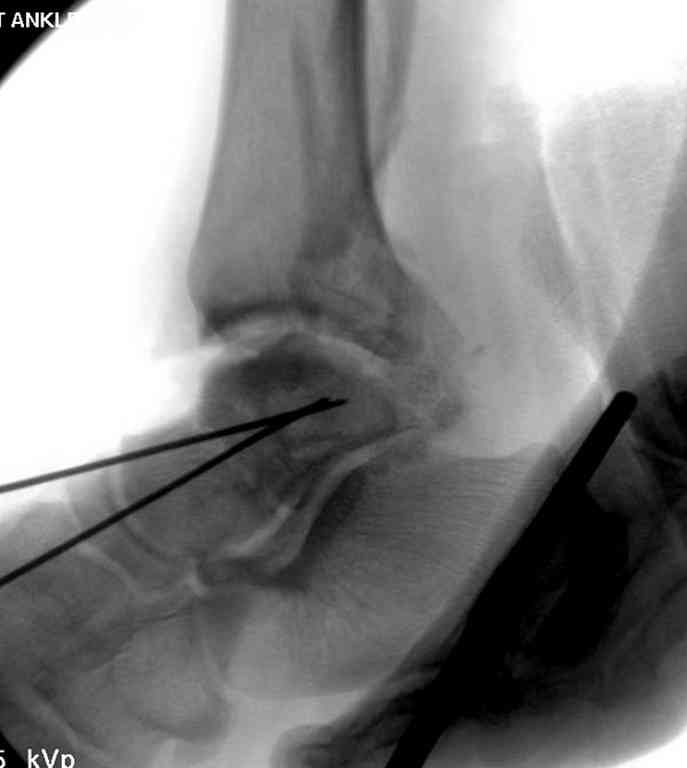

Здесь на фото примеры:

Переломовывих тарана с повреждением медиальной стороны. Через 4 часа после поступления проведена репозиция и фиксация тарана после Irrigation&Debridment. Частичное несращение медиальной лодыжки не беспокоит, вернулся к активному образу жизни. Полная нагрузка разрешена через 11 недель. Финальные снимки через 11 месяцев.

Второй случай прооперирован вчера.

10 дней назад поступил с открытым повреждением медиальной лодыжки и переломо вывихом таранной кости. Ургентно сделана репозиция с наложением наружного фиксатора + Irrigation&Debridment.

Во время репозиции выявили повреждение заднего сухожилия м. тибиалис и задней большеберцовой артерии. Медиальную рану удалось закрыть частично и установлен вакуум.

Дважды провели Irrigation&Debridment с заменой вакуума.

Вчера провели фиксацию.